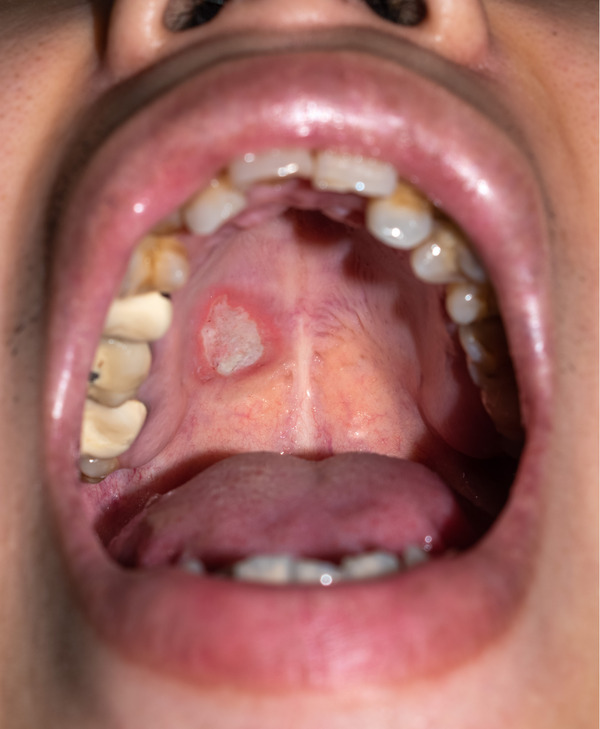

1. Check Your Mouth Regularly – look for unusual changes, such as sores, white or red patches or lumps.